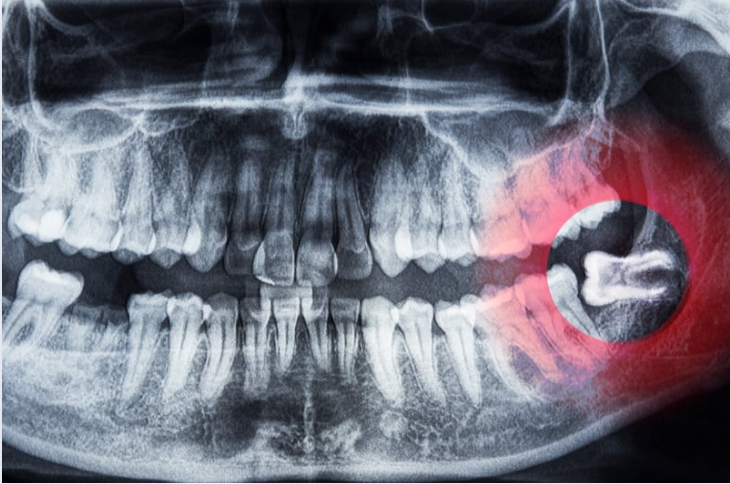

The last teeth in your mouth to develop, wisdom teeth often do not have enough room to fully erupt or may be positioned in the wrong direction. These issues can affect your dental health as well as overall wellbeing. While some individuals never develop all their wisdom teeth, and a few have sufficient space for them, there are many people with partially or fully impacted third molars. Our office will monitor the development, position, and health of your wisdom teeth and will advise you if and when extractions are indicated.